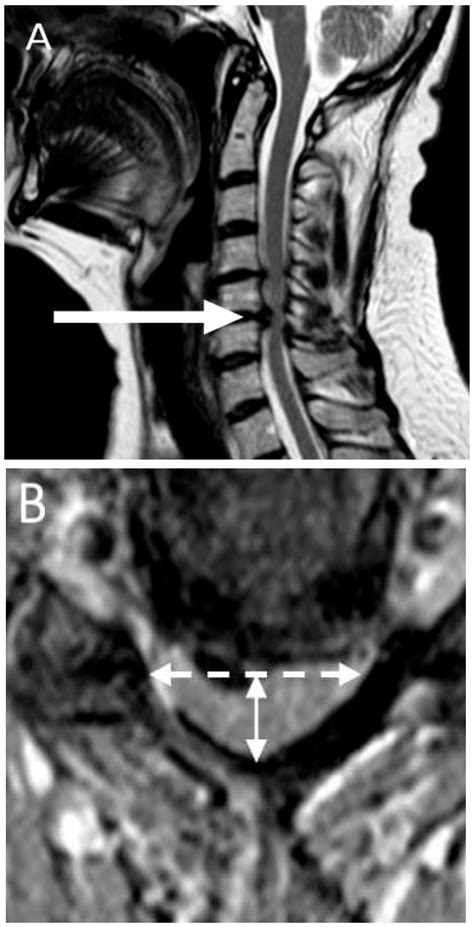

• Imaging: X-rays, MRIs, or CT scan to identify structural abnormalities, such as disc herniations or arthritis.